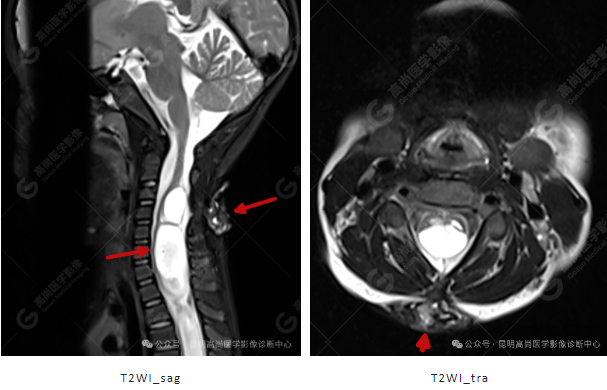

患者女,5 岁,出生时发现颈部包块,大小 3 cm×3 cm,5 年来无变化,拟行手术治疗,要求增强核磁协诊,否认体内金属物,无过敏史。

影像表现

颈 3-5 层面颈后部软组织不规则片状异常信号影,脊膜膨出可能;颈 3、4 棘突局部显示不清;颈胸髓内(约颈 3-胸 9 椎体水平)异常信号影,考虑囊肿并局部颈髓空洞可能,肿瘤或其他待排;请结合临床及相关检查。